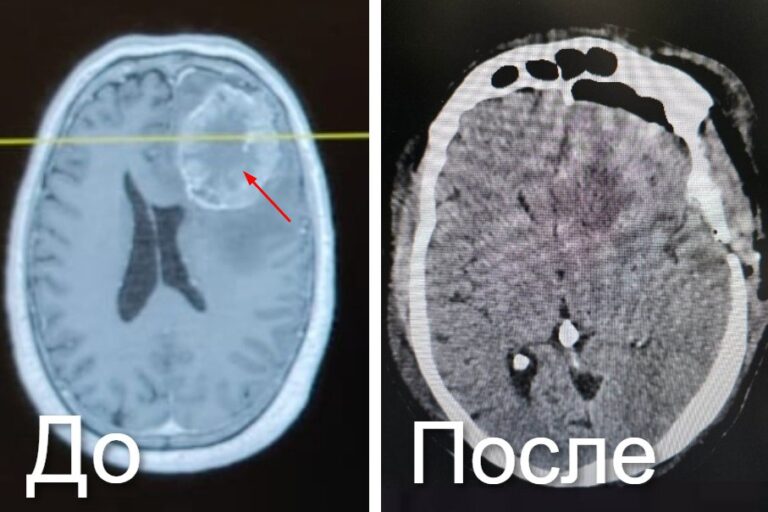

Специалисты городской клинической больницы №1 имени Г.П. Курбатова удалили опухоль желудка 66-летнему мужчине с помощью тоннельной резекции. Такую операцию называют «хирургией..